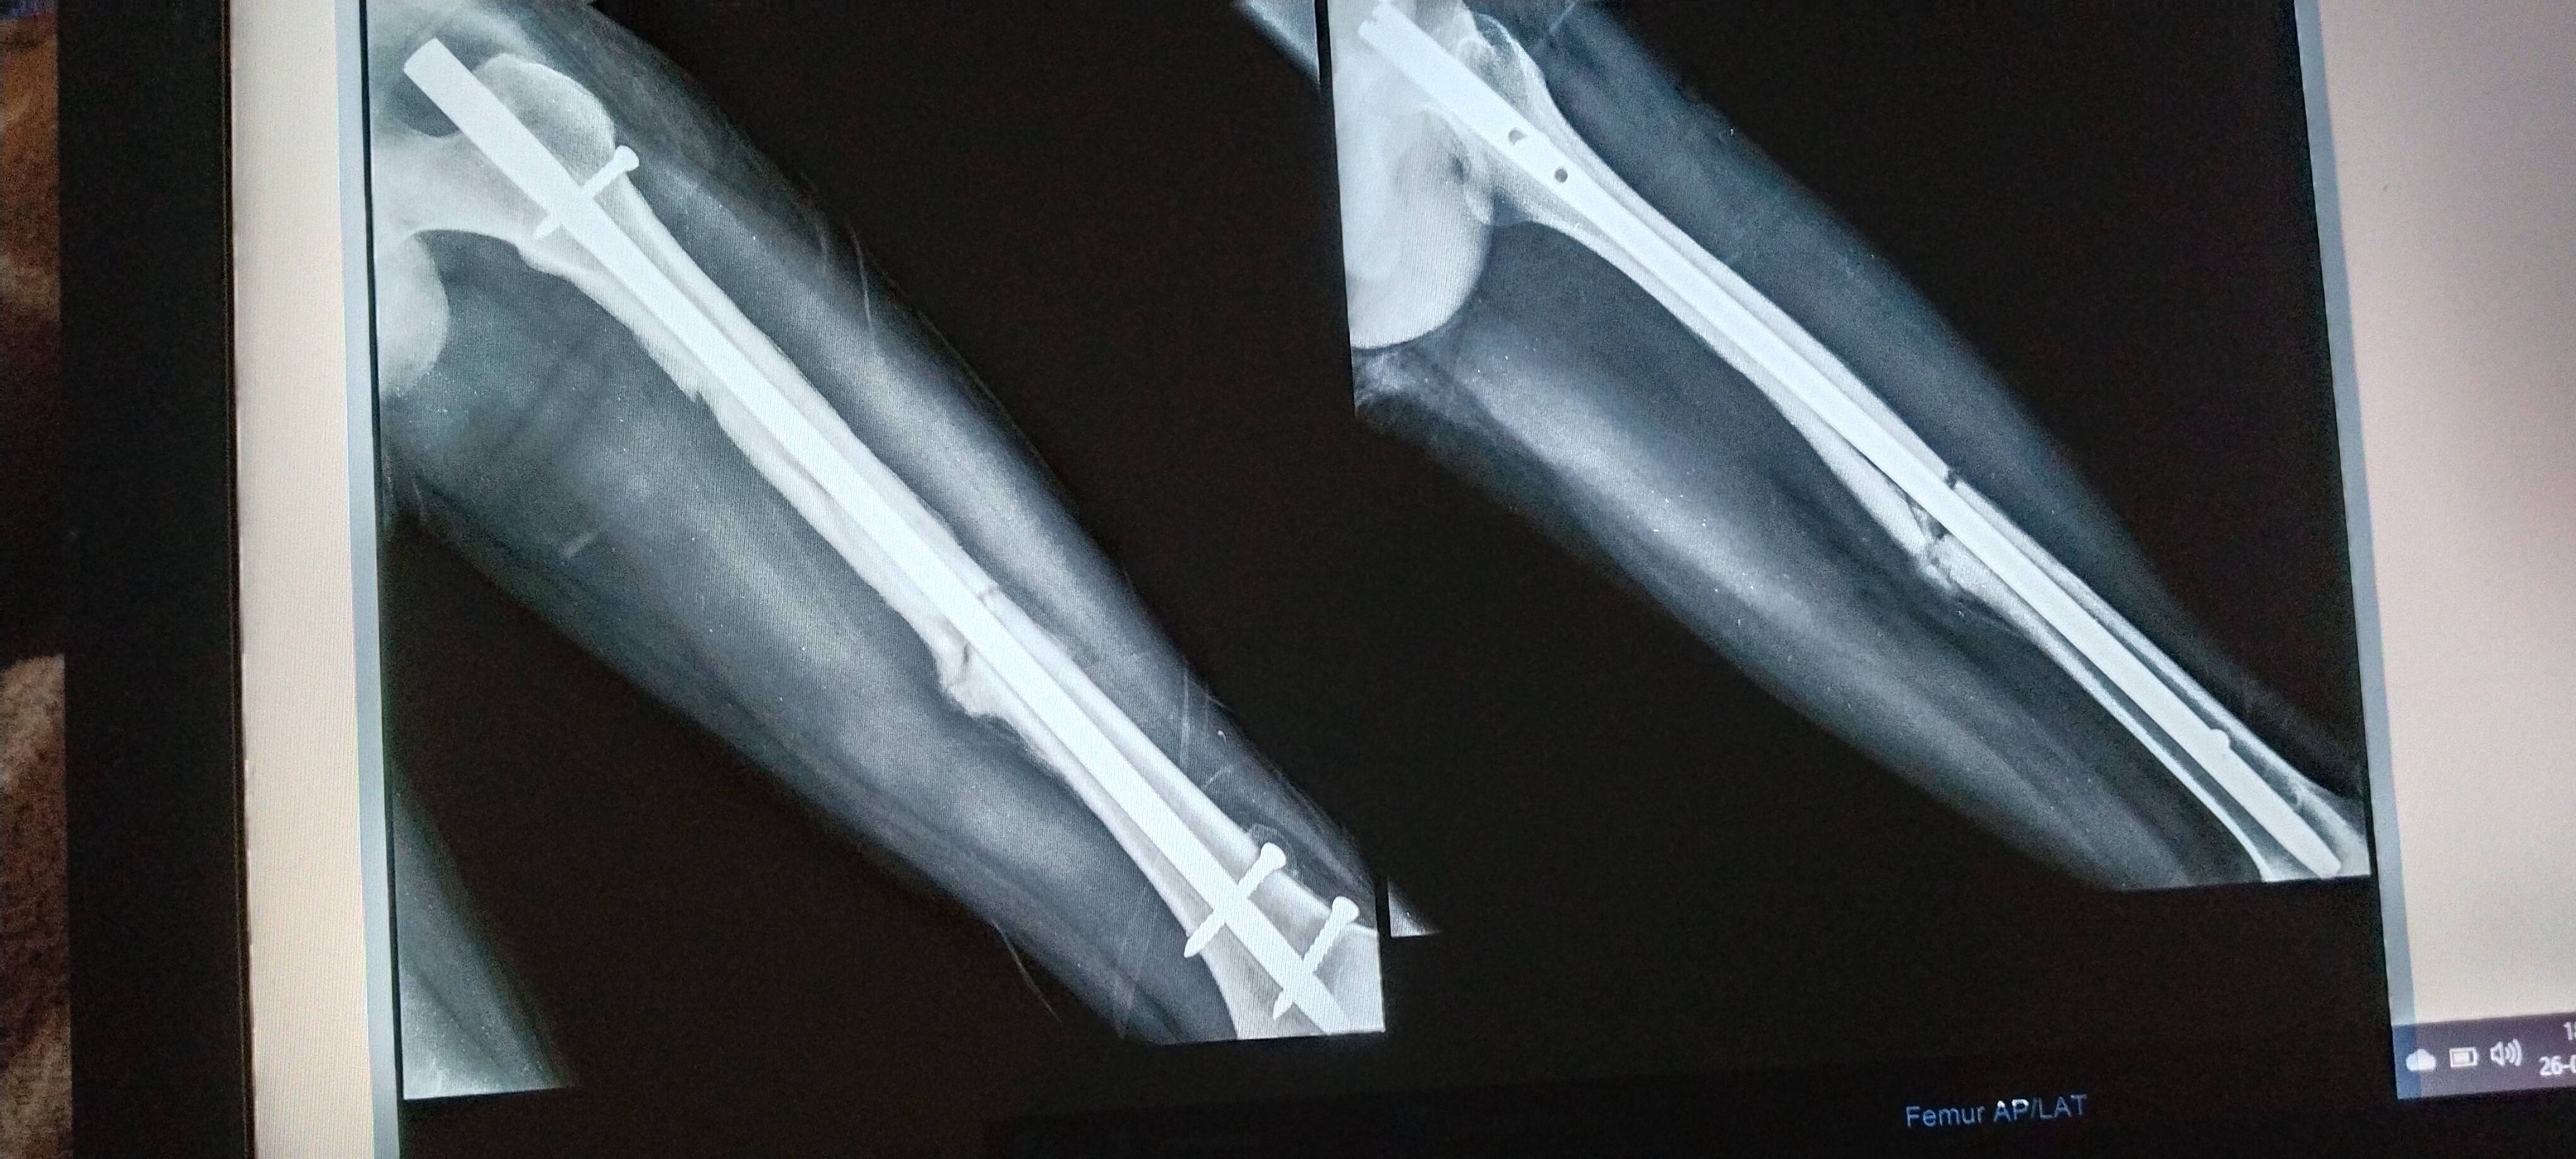

Sir this one is x ray after 5 month 11 days of surgery

will this bone unite or need bone grafting

ORIF has been done in this case